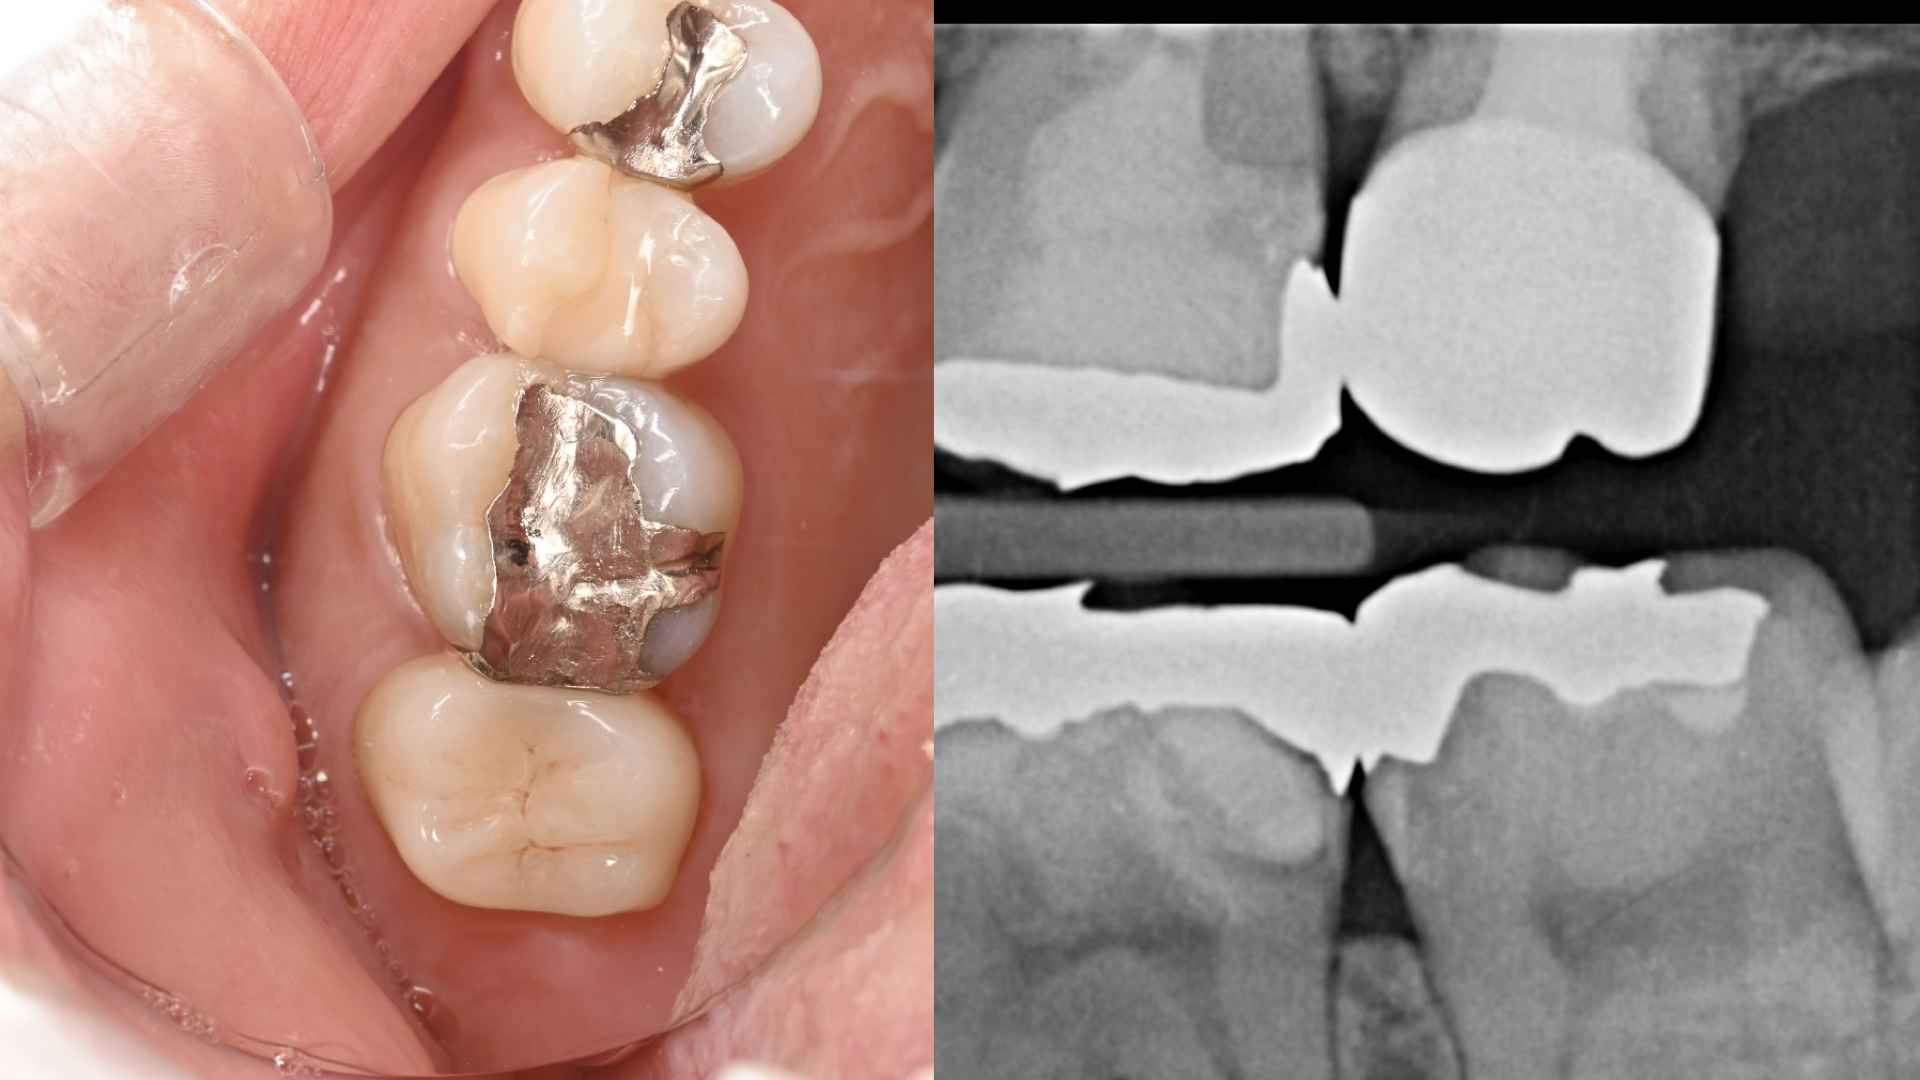

抜歯と言われた奥歯の症例

初診時

- 40歳 女性 パーソナルトレーナーさん

- 左上の奥歯の痛みで1年前に近医を受診、この時点で大学病院を勧められていた。治療に3ヶ月かかり、その後7ヶ月で再度炎症を起こした。抗生剤の服薬で収めていた。その後2ヶ月後に2回目の再炎症を起こした。抜歯または、大学病院を勧められた。大学病院は、3ヶ月後に初診を予約している。2回目の再炎症の際がピークで、左上を中心とした顔面の痛み、頭痛があった。抜歯と言われたが抜かない方法を考えている。歯の土台に太い金属が入っているため、治療方法、保険、自費根管治療の違いや歯の生存率も踏まえて知りたい。

CT(3次元レントゲン)診査

- 歯の状態:歯質が骨縁上に適切な厚みを持って存在する。根尖の外部吸収様所見

- 隣在歯の状態:失活しているが、病変は認めない。

- 歯根の外部吸収を伴う根尖性歯周炎

- 上顎洞炎を伴う根尖性歯周炎